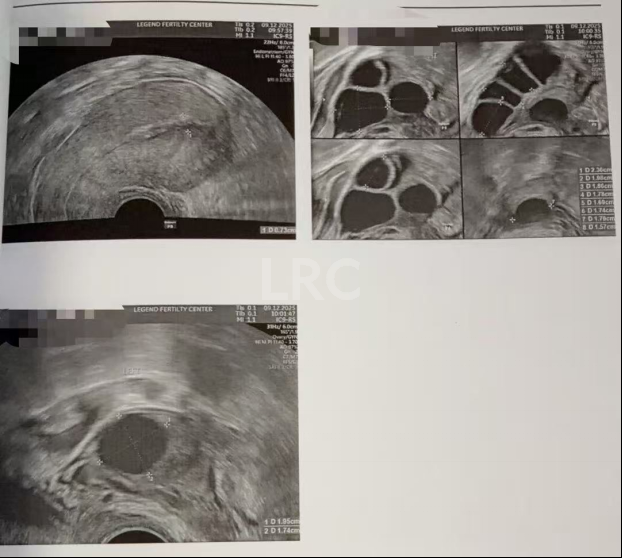

月经第二天 促排第一天

阴超检查:基础卵泡 6 颗

-右侧 3 颗 (4,3,3mm)

-左侧 3 颗 (5,4,3mm)

激素水平检查:

-促黄体生成素 3.00miu/ml

-雌二醇25pg/ml

-促卵泡生成素 9.00miu/ml

-泌乳素 16.50ng/ml

子宫内膜厚度:7.20mm

促排第四天

阴超检查(只数能用卵子):

- 右侧可用卵泡 1 颗(9mm)

- 左侧可用卵泡 1 颗 (10mm)

- 促黄体生成素 5.00 miu/ml

促排第六天

阴超检查:

- 右侧卵泡 1 颗可用 (11,6mm)

- 左侧卵泡 1 颗 (13mm)

- 促黄体生成素 2.20 miu/ml

- 雌二醇 138.5 pg/ml

子宫内膜厚度:5.6 mm

促排第九天

- 右侧卵泡 1 颗可用 (17,8,8,7,5mm)

- 左侧卵泡 1 颗 (19mm)

- 促黄体生成素 4.40 miu/ml

- 雌二醇 529 pg/ml

子宫内膜厚度:8.9 mm

促排第一天

-右侧 5 颗 (10,9,8,7,6mm)

-左侧 2 颗 (5,2mm)

促排第三天

- 右侧可用卵泡 8 颗(16,12,11,10,9,8,8,8mm)

促排第七天

- 右侧卵泡 9 颗可用 (20,17,16,16,15,15,13,13,12mm)

- 左侧卵泡 2 颗 (15,19mm)

子宫内膜厚度:10 mm

促排第八天

- 右侧卵泡 9 颗可用 (22,21,19,19,17,17,17,15,15mm)

子宫内膜厚度:8.3 mm